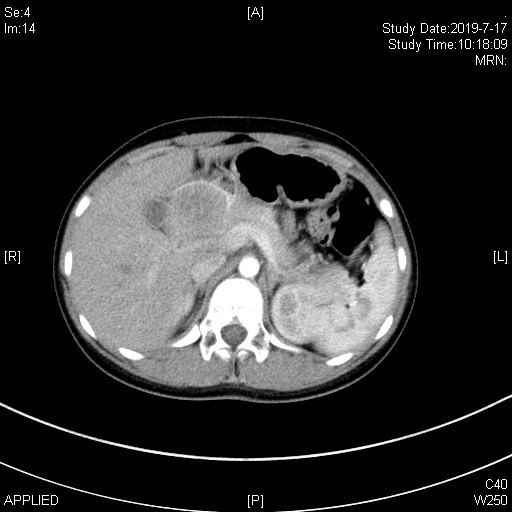

患者张**,女,11岁8个月,因“上腹部胀痛不适3个月”就诊当地医院,腹部ct提示胰头巨大肿瘤、压迫周围血管并导致肠系膜上静脉狭窄变型。为手术治疗转诊我院!

术前ct:

患者术前诊断考虑“胰头巨大实性假乳头状瘤”,治疗需行胰十二指肠切除术!但该手术风险大,术后并发症发生率高,且患者肿瘤巨大、压迫血管致手术难度增加;患者年龄较小,围手术期治疗棘手!为此,我们做了充份的预案!于2019年7月24日成功进行了保留幽门的胰十二指肠切除术(保留幽门可最大程度保留营养吸收,为患者以后生长发育提供条件)。